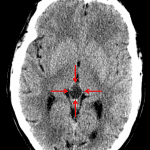

Age: 47

Sex: Male

Indication: Trauma

Case #12

Findings

- No acute intracranial abnormality

- Peripherally calcified low density lesion in the pineal gland

- Intracranial atherosclerosis

- Left maxillary and right frontal sinus polyps/mucous retention cysts

Diagnosis

- Incidental pineal lesion

No acute intracranial abnormality.

Peripherally calcified low density lesion in the pineal gland measuring x by x. Recommend nonemergent brain MRI with and without contrast for further evaluation.

Intracranial atherosclerosis.

Left maxillary and right frontal sinus polyps/mucous retention cysts.